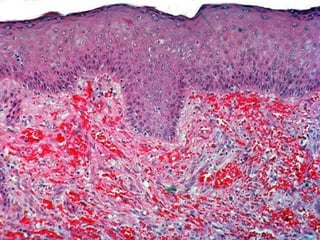

BULLOUS DISEASES •PEMPHIGUS(VULGARIS) • BULLOUS PEMPHIGOID • DERMATITIS HERPETIFORMIS • EPIDERMOLYSIS BULLOSA • PORPHYRIA • “ACANTHOLYSIS” is the common unifying finding, as is basement membrane immunoglobulins

• #84 Know the various types of “bullous” diseases. What is a bulla? What is acantholysis?

• #85 Pemphigus, ruptured, scabbed bullae

• #86 Pemphigus, fresh bullae

• #87 Acantholysis in the bullous family of diseases